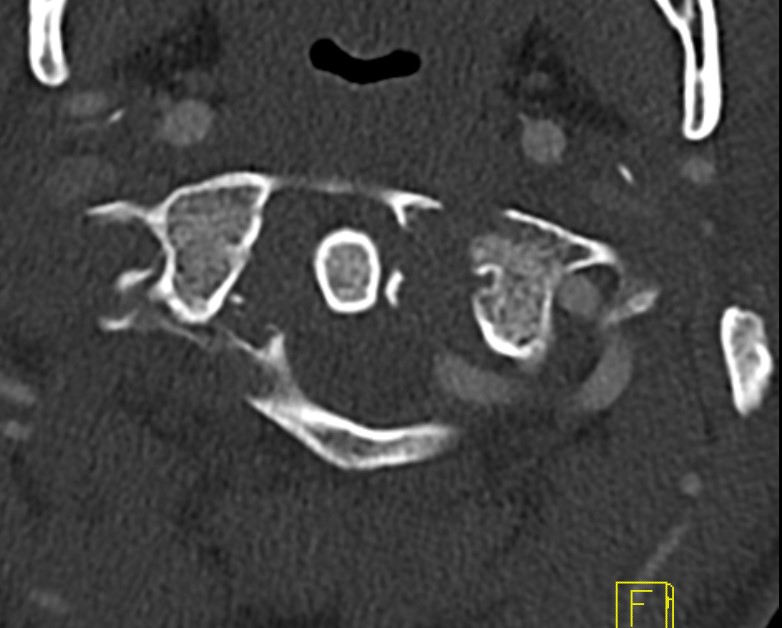

CT

Better defines displacement, ADI, LMD and bony avulsions of the transverse ligament

Avulsionlig avulsion

CT axial slices "Jefferson" (burst) fracture with bony avulsion (blue) of the transverse ligament

CT LMDCT Jefferson